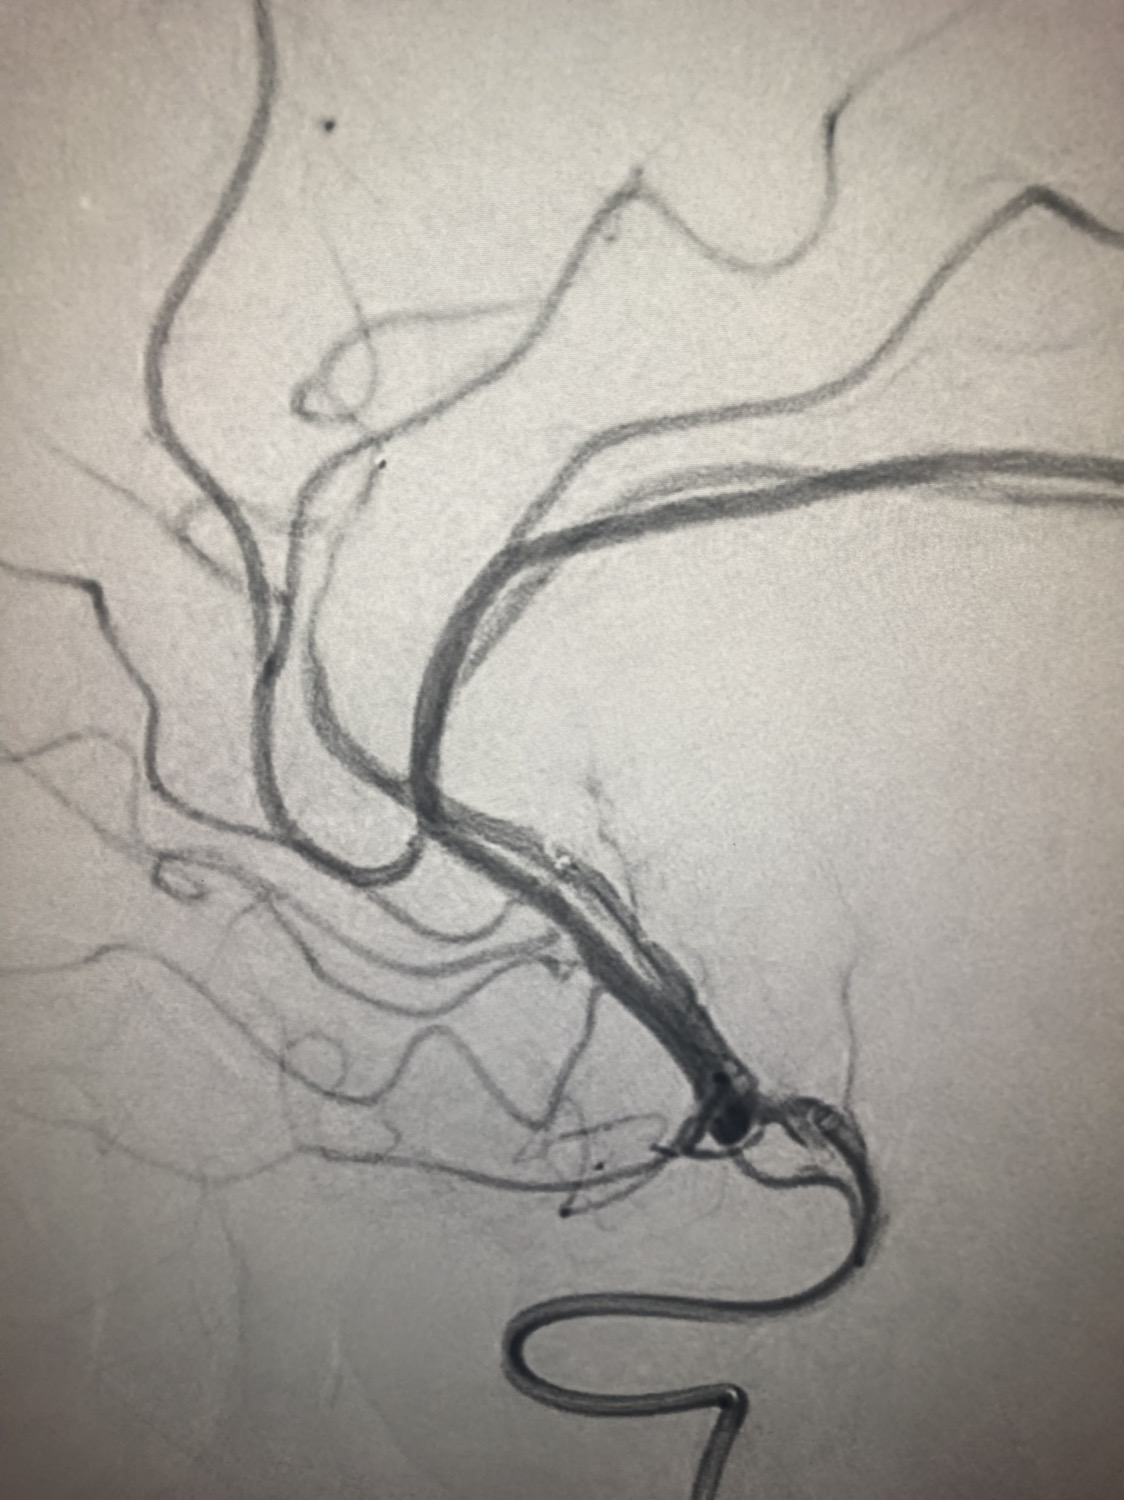

急诊二。zde,f53y。

意识模糊进行性加重8h,基底动脉闭塞,reco取栓再通,貌似动脉硬化,实际血管光滑。造影➕取栓8min。今日团队配合紧密,不到三小时全麻造影取栓带苏醒完成两台取栓。团队棒棒的!南阳市中心医院神经内科脑血管病介入团队